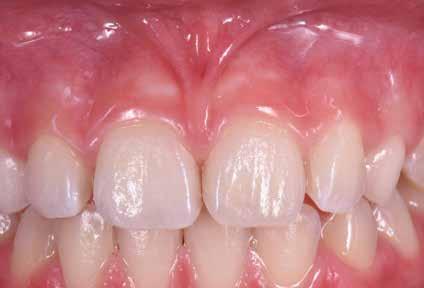

B.M. Bambina di sei anni e mezzo, con malocclusione scheletrica di II Classe, deep-bite over-jet elevato, lieve contrazione dell’arcata superiore, alterazione dell’eruzione dell’elemento dentale 21.

Fig. 122 > Immagine intraorale frontale.

Fig. 123 > Immagine intraorale laterale destra.

Fig. 124 > Immagine intraorale laterale sinistra.